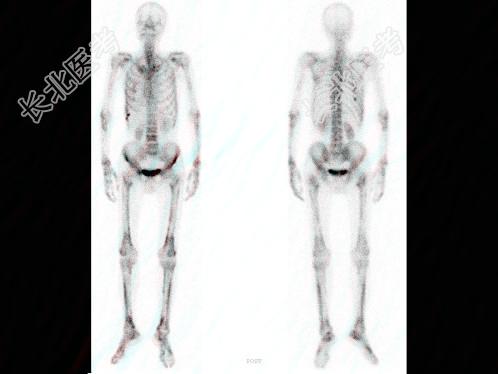

- 多项选择题男,68岁, 肺癌术后半年,诉双下肢疼痛3个月, 行全身骨显像如图,可能的诊断是 ( )

A、双侧下肢骨骨转移瘤

B、热髌征存在

C、广泛骨转移瘤

D、双下肢肥大性骨关节病